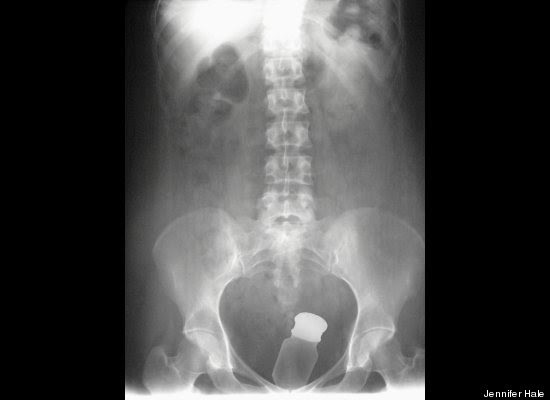

"Stack Up!" es una muy divertida colección de 100 imágenes de rayos X que muestra cuerpos extraños ingeridos o insertados en el cuerpo humano, tanto por accidente o de forma voluntaria, aunque se haga difícil imaginar el motivo de algunas de tales inserciones.

Los autores del libro -dos psiquiatras y un médico de sala de emergencias- aseguran -sin mucha originalidad pero con conocimiento de causa, que la imaginación humana no tiene límites. Esta afirmación es aplicable tanto a la calidad y variedad de objetos tragados o incorporados al cuerpo, como a los motivos o excusas utilizados para justificar la presencia de dichos objetos.

"Hay gente que hace cosas realmente imprudentes, y luego trata de racionalizarlas", advierten los autores en la solapa del libro, destacando precisamente la imaginación humana para "dar con usos imprevistos para objetos de la vida cotidiana".

"Tenía las manos ocupadas", "me caí encima", son algunas de las excusas que los profesionales de la salud escuchan de los pacientes que llegan a los hospitales con "cuerpos extraños extrañamente metidos en el cuerpo".

Redactado de manera humorística, el libro se pregunta cómo un teléfono celular puede haber ido a parar al sitio de la anatomía del propietario donde nunca da el sol, respondiéndose que, probablemente, estuviera en modo vibrador.

"Hallar un termómetro atascado en el recto de un adulto puede resultar corriente. Pero ¿Qué se puede decir de una muñeca Barbie, perteneciente a su hija de seis años?", se preguntan los autores, añadiendo el consejo infaltable: no hagan esto en casa.